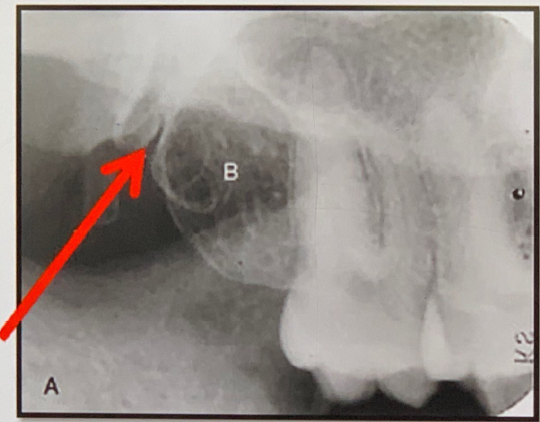

84. What is the anatomical structure indicated by arrow in this radiograph?

Maxillary Sinus The borders of the maxillary sinus appear on periapical radiographs as a thin, delicate, tenuous radiopaque line. In adults the sinuses usually extend from the distal aspect of the canine to the posterior wall of the maxilla above the tuberosity. In older adults the sinus may extend farther into the alveolar process, and in the posterior region of the maxilla its floor may appear considerably below the level of the floor of the nasal cavity. Anteriorly each sinus is restricted by the canine fossa and is usually seen to sweep superiorly, crossing the level of the floor of the nasal cavity in the premolar or canine region. Consequently, on periapical radiographs of